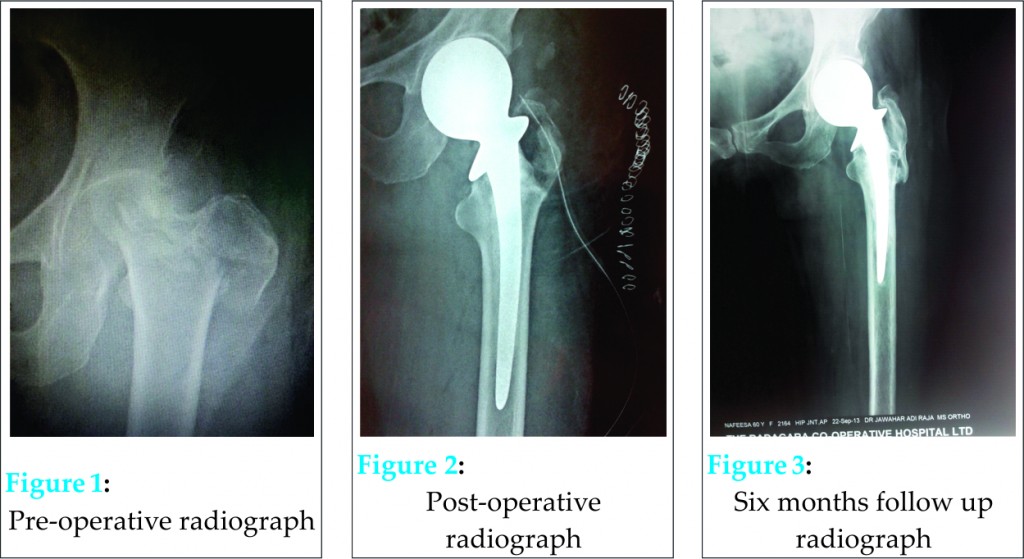

A 60 year old lady was brought to our hospital casualty in March 2013 after a fall. She gave history of a sudden twist while climbing stairs following which she fell down. On examination she was conscious and oriented; but unable to move her left lower limb which was rotated externally and about 4 centimeter shorter. Left pubic region showed fullness with palpable rounded bony mass and more prominent femoral artery pulsation. Radiograph (Fig.1) showed dislocation of hip with fracture of trochanter extending through neck of femur to the base of the head. There was no fracture in any other bones of the limb. Neurovascular structures were clinically intact. Patient was immediately worked up for surgery and she underwent cemented hemiarthroplasty using Thompson Prosthesis. Posterior approach was opted to prevent neurovascular injury from distorted anterior anatomy and also because surgeons were more familiar with that approach. Fracture line was found extending from greater trochanter laterally passing obliquely and proximally to end at the base of the head of the femur. Greater trochanter was found avulsed as a separate fragment. At the end of six months patient had painless hip with near normal range of movements and an acceptable gait.

Dislocation of hip usually occurs as a result of high energy trauma and is often associated with injury to head of femur or acetabulum [4]. An additional acetabular fracture occurs if longitudinal forces are stronger than adduction forces. But if longitudinal force is combined with adduction force, neck of femur gets fractured especially in osteoporotic bone [5]. Our patient might have been subjected to considerable rotational force which caused this very rare pattern of injury. We believe that first mechanism was longitudinal force which was then supervened by adduction and external rotation force leading to anterior dislocation of hip and associated fracture of neck and trochanter of the femur. Such injuries are orthopedic emergencies and require immediate surgical intervention [5].Up to 1/3 of these cases can lead to osteonecrosis of the head of the femur especially if associated with severe bone destruction as in our case [2]. As there was comminution of trochanter and the entire neck was involved by the fracture pattern, open reduction was not attempted. Head of the femur along with attached part of the neck was removed. Remnant neck was nibbled out and cemented hemiarthroplasty performed (Fig.2). The avulsed greater trochanter fragment which got fallen back by itself after reduction of the hip was stabilized with thick (No.1) absorbable sutures of Monofilament Polydioxide (PDS) material. Walker assisted mobilization was started on 5th post-operative day;non-weight bearing for three weeks and then gradually increasing partial weight bearing walking. At six months follow up after surgery, the radiograph (Fig.3) of the operated hip showed near normal joint anatomy and good functional outcome.